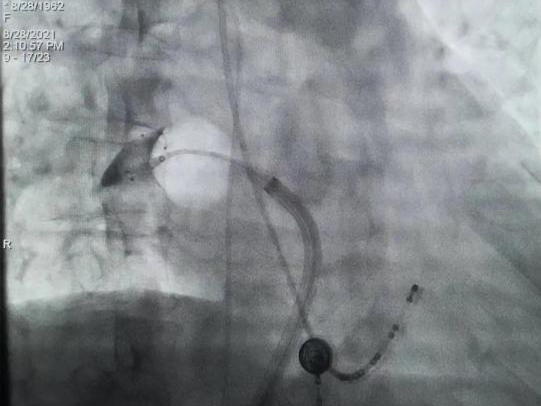

2021年8月28日上午10点,手术正式开始。食管彩超显示左心耳无血栓,李耀东教授带领奎屯医院心内科王飞、杨鸿英、张娟医生进行房间隔穿刺,左心耳造影结果显示为鸡翅型左心耳,在测量左心耳开口宽度和深度后,确定锚定区与封堵区,李教授选择了LAmbre™ 2430封堵器,经输送鞘管送至左心耳实现封堵。造影及食道超声显示均无残余分流,牵拉测试稳定,符合COST原则,释放后取得了理想的封堵效果。随后李耀东教授带领团队对患者4条肺静脉进行冷冻消融,手术历时2小时顺利成功,术后第二日患者活动正常,身体恢复良好。